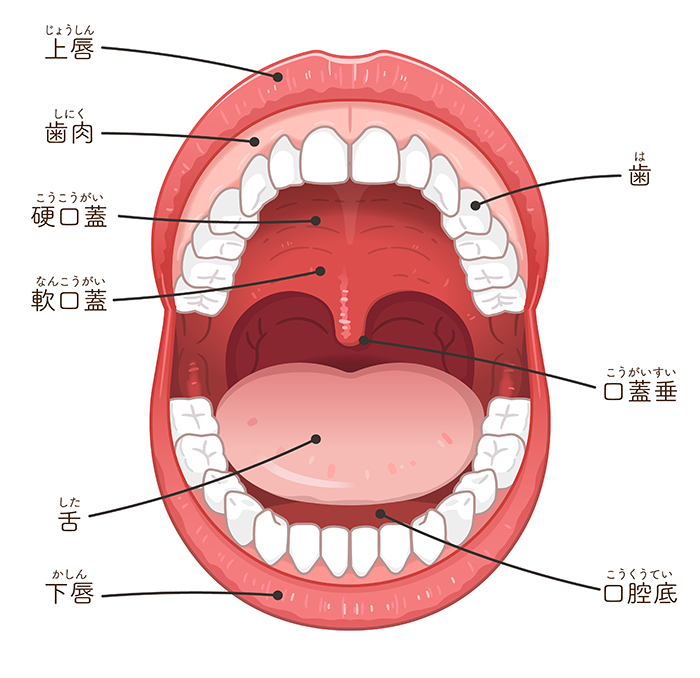

歯肉の下がった箇所の歯肉を歯の上部まで引っ張りあげ、患者さまご自身の上顎の口蓋部(硬口蓋と軟口蓋を合わせた部分)より採取した結合組織を移植します。場合により、歯周組織の再生を促す再生用材料であるEmdogain Gelを使用することもあります。